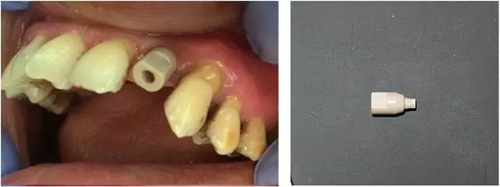

3個月后,分別使用傳統(tǒng)的轉(zhuǎn)移桿硅橡膠取模以及口內(nèi)掃描取模進行修復(圖5~8)。

圖5 進行口內(nèi)掃描

圖6 口內(nèi)掃描牙齦袖口

圖7 掃描專用基臺

圖8 口內(nèi)掃描照片(上頜)